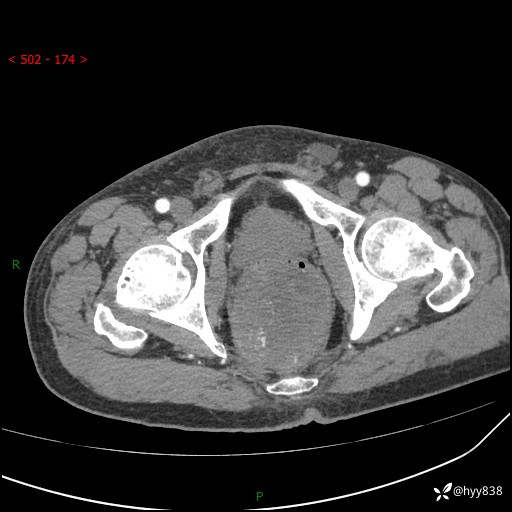

盆腔CT平扫+增强